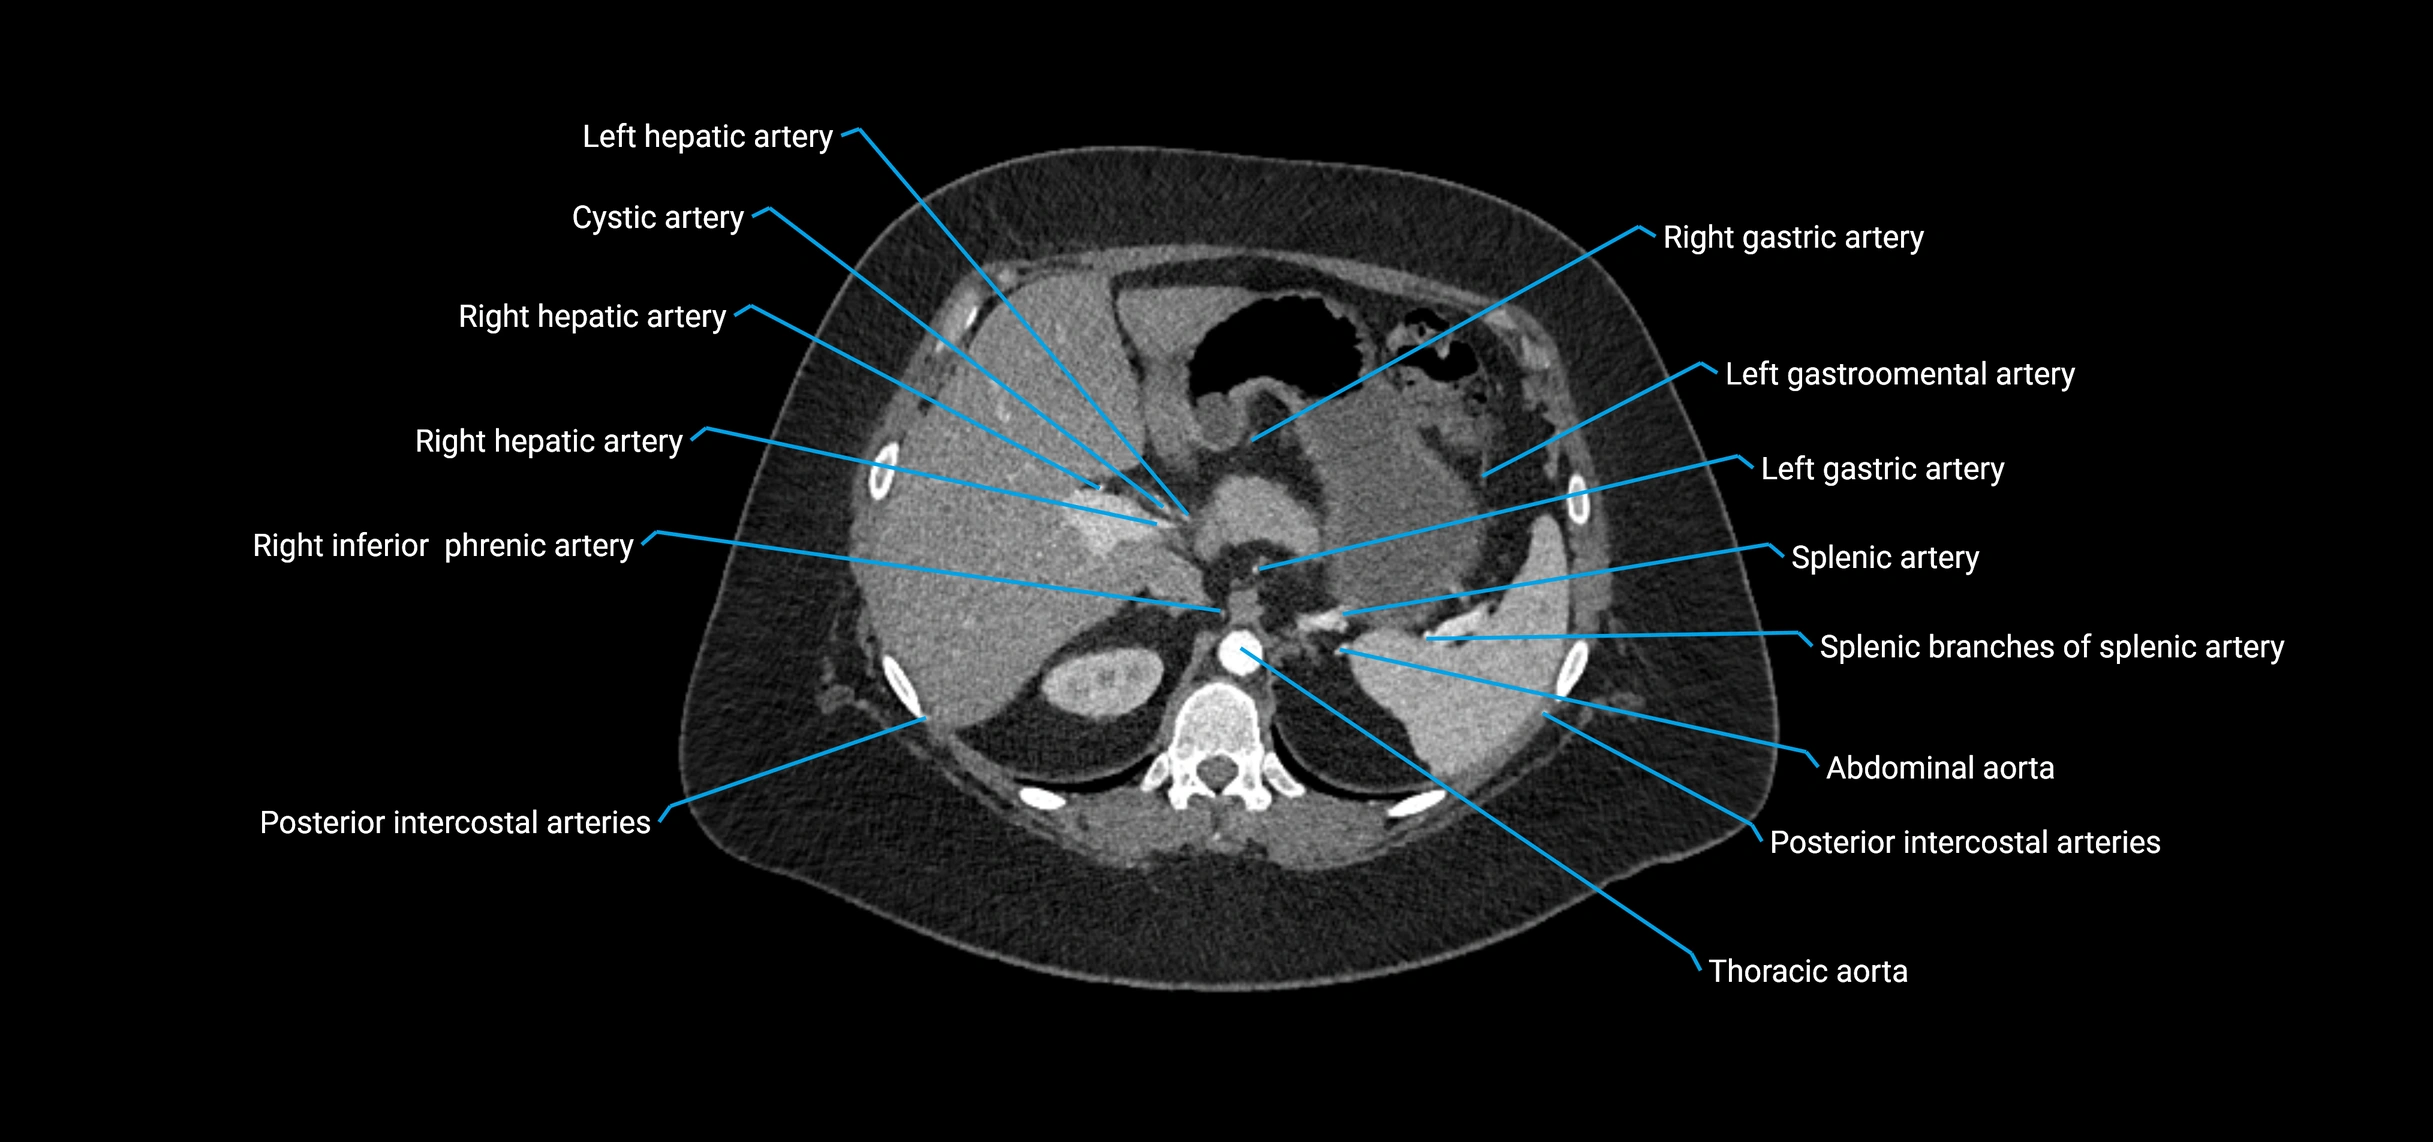

CT images

image